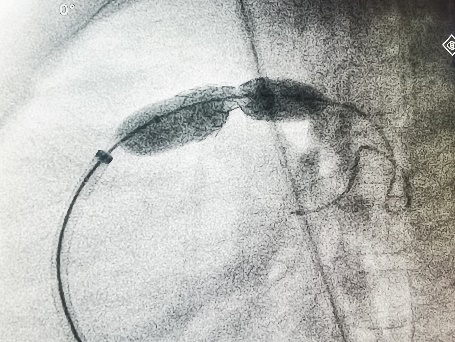

术前显示原植入支架断裂

在导丝引导下,右心导管通过断裂的支架,到达左肺动脉远端。再沿导丝送入Pul-Stent,和球囊载体,覆盖断裂的支架。

术中植入Pul-stent S20支架(EV3 10-3和12-3球囊)